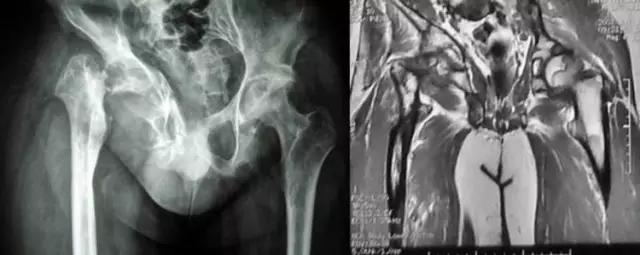

临床上以常见病为主,疑难病人不多,如果我们一下子就往疑难方面去想,反而容易进入死胡同。 病例:杨XX,男,25岁,右髋关节反复肿痛,逐渐丧失行走功能20年。辗转完国内著名医院就诊未果。只能考虑:慢性炎症?